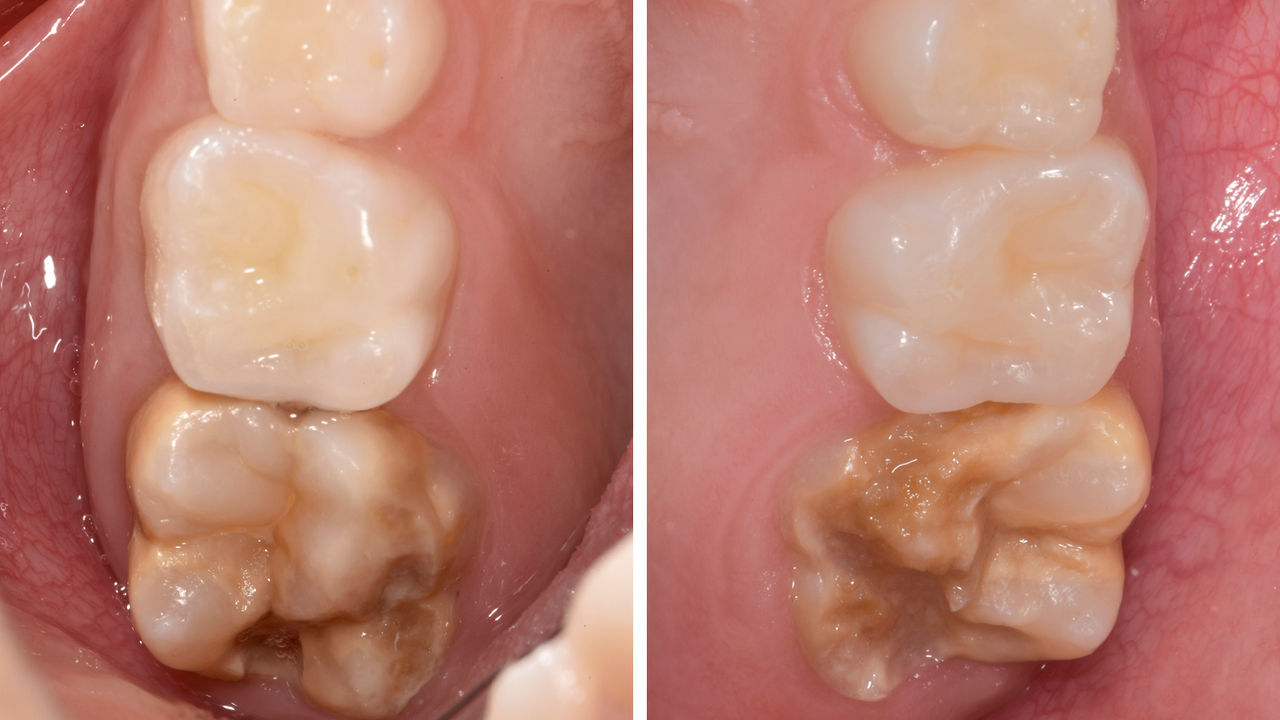

Before: Pre-operative clinical scenario after endodontic therapy.

After: 1 month after the CEREC Tessera onlay was bonded.